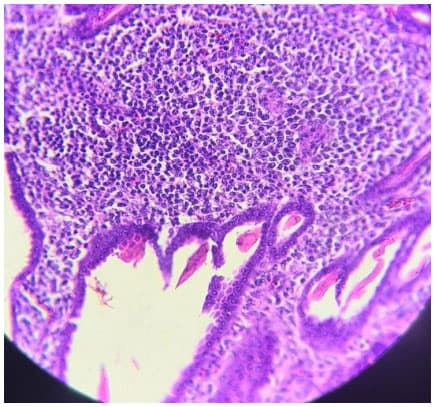

Infecções adenovirais são comuns em aves comerciais, principalmente em sistemas de criação intensificada e já foram reportadas em diferentes locais, como: Ásia, África, América do Norte, América do Sul e Europa. As doenças envolvendo os Aviadenovírus (FAdVs), incluem a hepatite por corpo de inclusão (HCI), síndrome da hepatite-hidro pericárdio, (SHH) e outras condições afetando o sistema respiratório e digestivo das aves, além da Síndrome de Erosão de Moela (SEM). Esta publicação objetiva a caracterização da SEM como condição emergente no Brasil. Foram analisadas, entre setembro de 2021 e maio de 2022, 168 aves em 56 casos, sendo estas tanto de corte como de reprodução. Foram conduzidos exames de PCR para identificar o DNA viral e 28 exames histopatológicos com alguns destes revelando presença de corpos de inclusão virais no ventrículo, além de quadros inflamatórios típicos envolvendo infiltrado linfoplasmohistiocítico. Foram encontrados outros processos inflamatórios em outros órgãos, como o pró-ventrículo. O PCR evidenciou positividade para o Aviadenovírus. Com base nos achados do presente estudo, caracterizou-se a presença da SEM no Brasil. Enfatizamos a importância do sequenciamento do vírus, especialmente do tipo 1, como próximo passo a ser seguido.